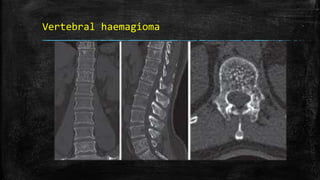

Vertebral haemagioma